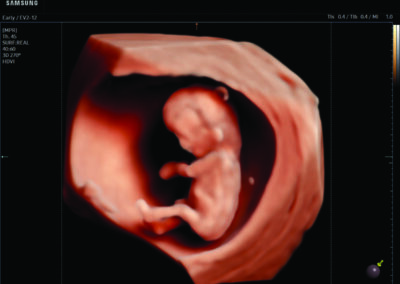

Comprehensive, advanced and expert MFM care for high-risk pregnancies